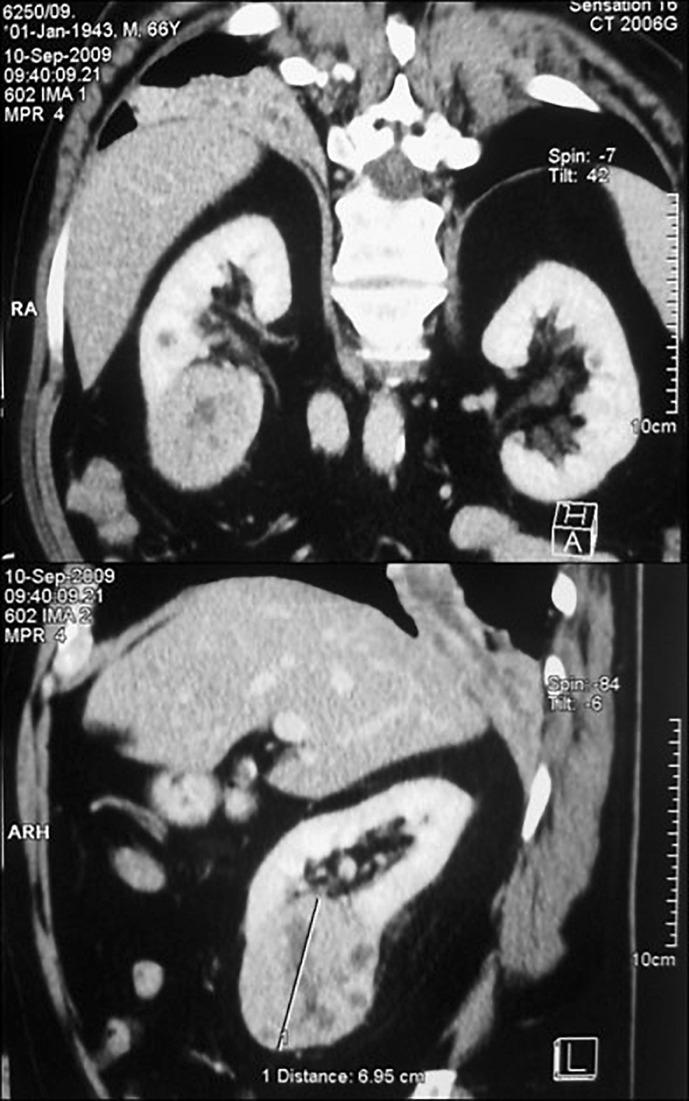

Solitary metastasis presented as a solid mass in the central third of the upper eyelid, which has been growing for 3 weeks. Treatment included tumor removal and blepharoplasty. Histopathological examination showed metastasis of clear cell renal carcinoma. A thorough examination revealed a primary tumor on the lower pole of the right kidney. A right nephrectomy was performed, and histopathology showed ccRCC. Postoperative examinations showed no signs of local or systemic disease. Sunitinib malate was administered to the patient.

孤立性转移表现为上睑中央三分之一处的实性肿块,已生长3周。治疗包括肿瘤切除和眼睑成形术。组织病理学检查显示为透明细胞肾癌转移。全面检查发现右肾下极有原发性肿瘤。行右肾切除术,组织病理学显示为ccRCC。术后检查未发现局部或全身疾病迹象。给予患者苹果酸舒尼替尼治疗。